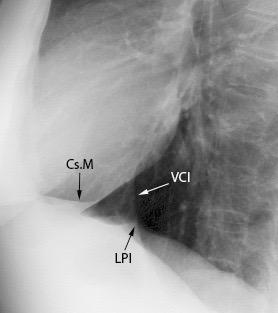

Diafragma izquierdo +/-16mm El ligamento pulmonar izquierdo (LPI) puede interrumpir la interfase normal pulmonar-diafragma obliterando un pequeño segmento

Proto AV,. The left lateral radiograph of the chest. Part One. Med. Radiogr. Photogr.1979.

Variante: Aire/grasa por delante de la VCI

Molinari F et al. Fat-containing Lesions in adult thoracic imaging. AJR.2011